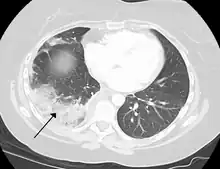

Tissue death of the lung due to a pulmonary embolism

A pulmonary embolism is a blood clot that becomes lodged in the pulmonary arteries. The majority of emboli arise because of deep vein thrombosis in the legs. Pulmonary emboli may be investigated using a ventilation/perfusion scan, a CT scan of the arteries of the lung, or blood tests such as the D-dimer.[76] Pulmonary hypertension describes an increased pressure at the beginning of the pulmonary artery that has a large number of differing causes.[76] Other rarer conditions may also affect the blood supply of the lung, such as granulomatosis with polyangiitis, which causes inflammation of the small blood vessels of the lungs and kidneys.[76]

A lung contusion is a bruise caused by chest trauma. It results in hemorrhage of the alveoli causing a build-up of fluid which can impair breathing, and this can be either mild or severe. The function of the lungs can also be affected by compression from fluid in the pleural cavity pleural effusion, or other substances such as air (pneumothorax), blood (hemothorax), or rarer causes. These may be investigated using a chest X-ray or CT scan, and may require the insertion of a surgical drain until the underlying cause is identified and treated.[76]